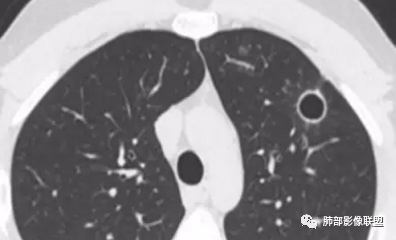

晨读:女,31,间断咳嗽、咳痰9月。卵巢交界性囊腺瘤术后。胸部CT:双肺多发大小不等薄壁囊腔影,部分融合,形态不规则,个别囊壁偏厚。右肺上叶及左肺下叶纤维索条影。左下叶不规则囊腔影,壁不均匀增厚,周围不规则实性成分加GGO,放射性毛刺,胸膜牵拉。考虑:囊腔型Ca?转移?鉴别PLCH,Lam,LIp,BHD,CF,CPAM等,听大咖解析。

3.BHD:多有家族史,可见皮肤纤维毛囊瘤、肺囊肿、自发性气胸、肾肿瘤,多位于肺基底部近胸膜下,形态不规则,可大可小,都有大的肺囊肿。不支持。

5.囊腔型肺转移瘤:常见于头颈部的鳞状上皮癌、胃肠道的腺癌、女性生殖系统肿瘤、肺外肉瘤的转移。

晨读病例有妇科肿瘤手术史,肺内病变转移瘤可能性大(而且一般盆腔肿瘤手术前基本都会完善胸部X检查,能够顺利完成手术估计手术时肺内无明显病灶),但肺囊肿有较明显的融合,这在转移瘤中较少见。综合上述考虑囊腔型肺转移瘤,鉴别PLCH。